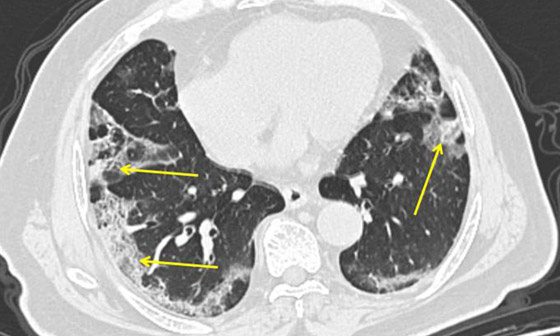

تصوير مقطعي محوسب من مستشفى جامعة جورج واشنطن يُظهر آثار فيروس كورونا المستجد، أو ما يُعرف بـ"كوفيد-19"  رئتي رجل عمره 59 عاماً. فشاهدوا معنا في الفيديو المدهش أدناه كيف تبدو رئة مصاب بفيروس كورونا (فيروس كوفيد 19) وما يحصل داخلها..